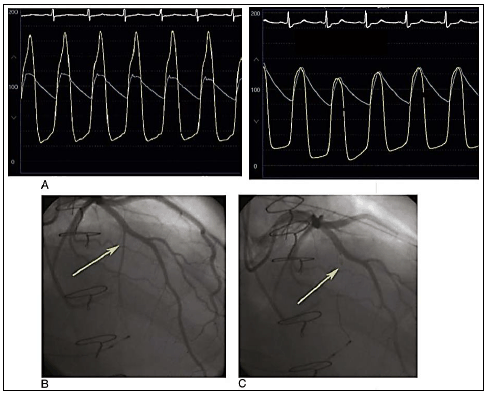

Homem, 53 anos, com quadro de dispneia e dor torácica sob investigação, realizou o seguinte procedimento para melhora do quadro atual:

Qual o diagnóstico etiológico mais provável?